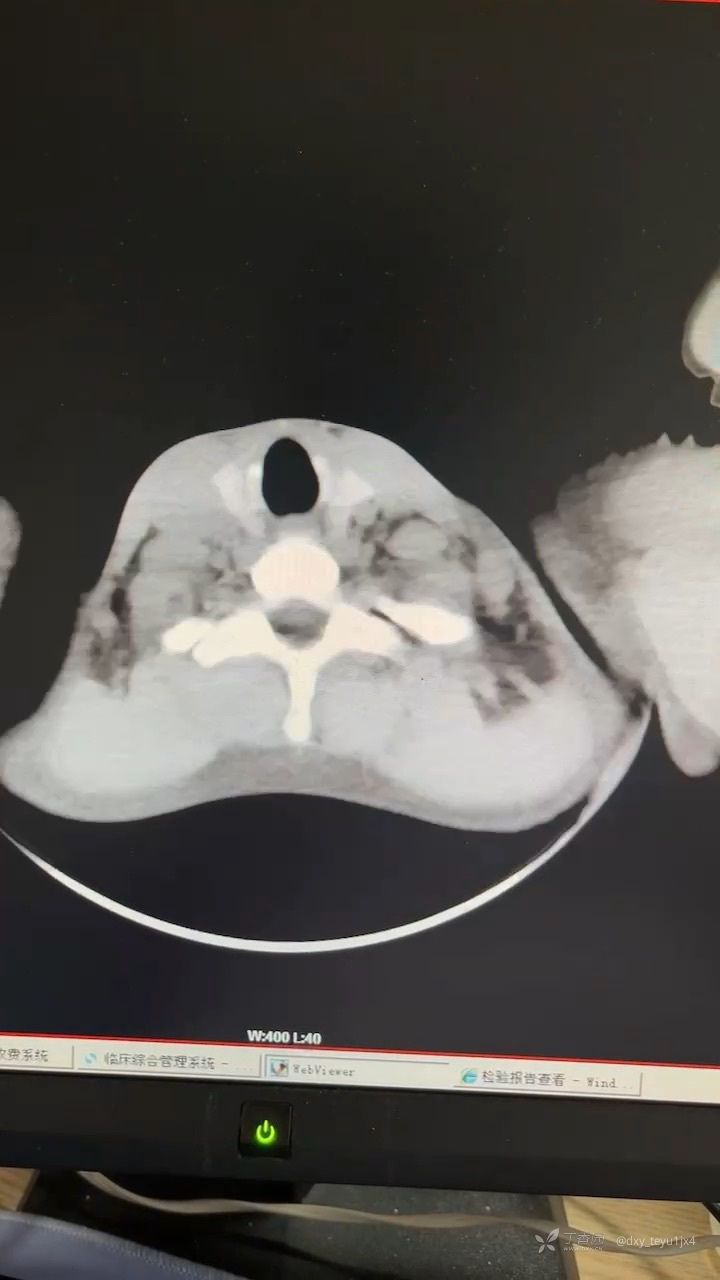

男 ,34岁,反复咳嗽咳痰 痰中带血2月 入院,伴有憋闷、气喘, ct提示双侧肺门增大,纵隔多发淋巴结肿大,petct 左肺下叶结节并阻塞性炎症,纵隔及左侧肋隔角病变 考虑肉芽肿性病变可能。